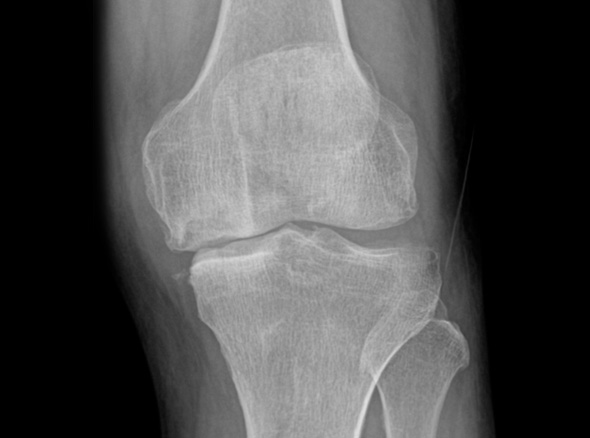

초기에는 수술이 아닌 비수술 치료만으로 생활에 불편함이 없도록

통증을 완화시키고 증상을 충분히 완화시킬 수 있습니다.

중기에는 비수술치료를 진행하고, 증상이 악화되는 경우 정상 조직을 최대한 보존하고 병변부위만 선택적으로 수술하는 관절내시경을 진행하게 됩니다.

말기의 퇴행성 관절염 환자에게 인공관절 수술은 최후의 수단으로 시행됩니다.